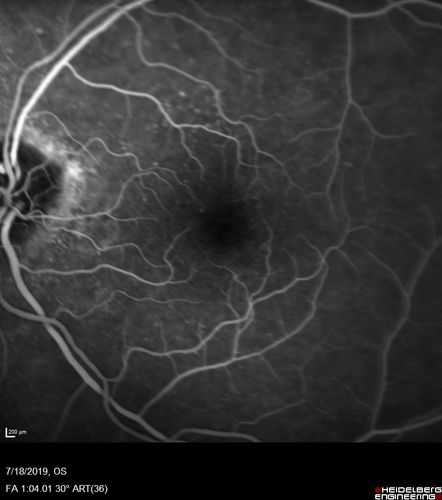

Stellate non-hereditary idiopathic foveomacular retinoschisis (SNIFR) and optic nerve drusen

84 year old man No visual complaints. Not diabetic, cataract surgery 8 years ago. Meds: Omeprazole, Tamsulosin (Flomax)

VA 20/32 OD, 20/20 OS